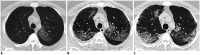

Pulmonary Fibrosis Due to COVID-19 Pneumonia